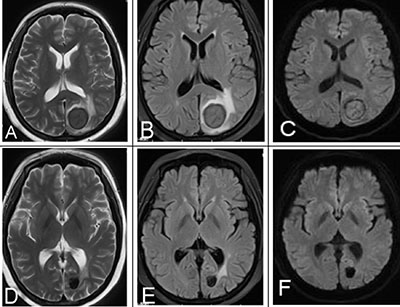

All patients underwent standard induction chemotherapy and intrathecal chemotherapy, and 4 patients also underwent radiation treatment. MRI follow-up was performed at 2 chemotherapy courses, 4 chemotherapy courses, 6 chemotherapy courses and after treatment. 80% of lesions achieved complete remission. MRI showed that these lesions turned into a cavity and were characterized by obvious hypointensity on T2WI/FLAIR and DWI versus pretreatment (Figure 3). 15% of lesions were further improved after 4 chemotherapy courses, as indicated by gradually lower MR signal intensities. 5% of lesions indicated residual disease after 6 chemotherapy courses, as indicated by hyperintensity on DWI, ADC map and CE-T1WI.

Figure 3: A 25-year-old female with a history of AML underwent chemotherapy and MRI follow-up. (A–C) MRI signal intensity was obvious and lower than pre-treatment on T2WI, FLAIR, DWI, indicating a good treatment response. (D–F) Post-treatment mass on T2WI, FLAIR, DWI.